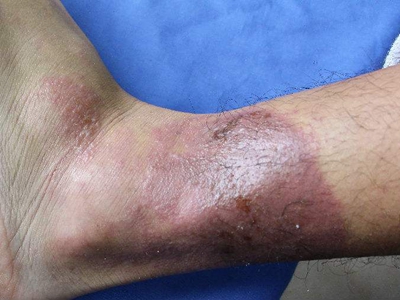

职业性光毒性接触性皮炎是职业性光接触性皮炎的一种类型,是指在职业活动中,接触光敏物(如煤焦沥青、煤焦油、蒽、氯丙嗪等),并受到日光(紫外线)照射而引起的皮肤炎症性病变。多发生在夏季,皮损只发生于暴露部位,有明显的光照界限。

职业性光毒性接触性皮炎多发于夏季。皮损只发生于暴露部位,有明显的光照界限。一般在接触光敏物及照光后数分钟到几小时后,呈急性炎症。轻者局部皮肤出现红斑、水肿伴有烧灼感;重者可在红斑水肿的基础上出现水疱,疱破后糜烂、结痂。常伴有眼结膜炎及全身症状。皮炎愈后留有弥漫性色素沉着,是职业性光毒性接触性皮炎的特点之一。